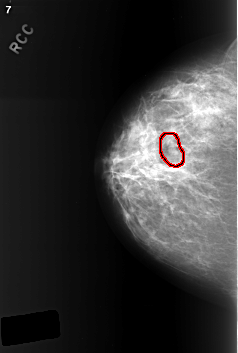

ics_version 1.0 filename C-0402-1 DATE_OF_STUDY 9 1 1996 PATIENT_AGE 49 FILM FILM_TYPE REGULAR DENSITY 2 DATE_DIGITIZED 15 10 1998 DIGITIZER LUMISYS LASER SEQUENCE LEFT_CC LINES 5552 PIXELS_PER_LINE 4056 BITS_PER_PIXEL 12 RESOLUTION 50 NON_OVERLAY LEFT_MLO LINES 5440 PIXELS_PER_LINE 3984 BITS_PER_PIXEL 12 RESOLUTION 50 NON_OVERLAY RIGHT_CC LINES 5640 PIXELS_PER_LINE 3800 BITS_PER_PIXEL 12 RESOLUTION 50 OVERLAY RIGHT_MLO LINES 5448 PIXELS_PER_LINE 4000 BITS_PER_PIXEL 12 RESOLUTION 50 OVERLAY |

FILE: C_0402_1.RIGHT_CC.OVERLAY TOTAL_ABNORMALITIES 1 ABNORMALITY 1 LESION_TYPE MASS SHAPE LOBULATED MARGINS CIRCUMSCRIBED ASSESSMENT 3 SUBTLETY 4 PATHOLOGY BENIGN TOTAL_OUTLINES 1 BOUNDARY |